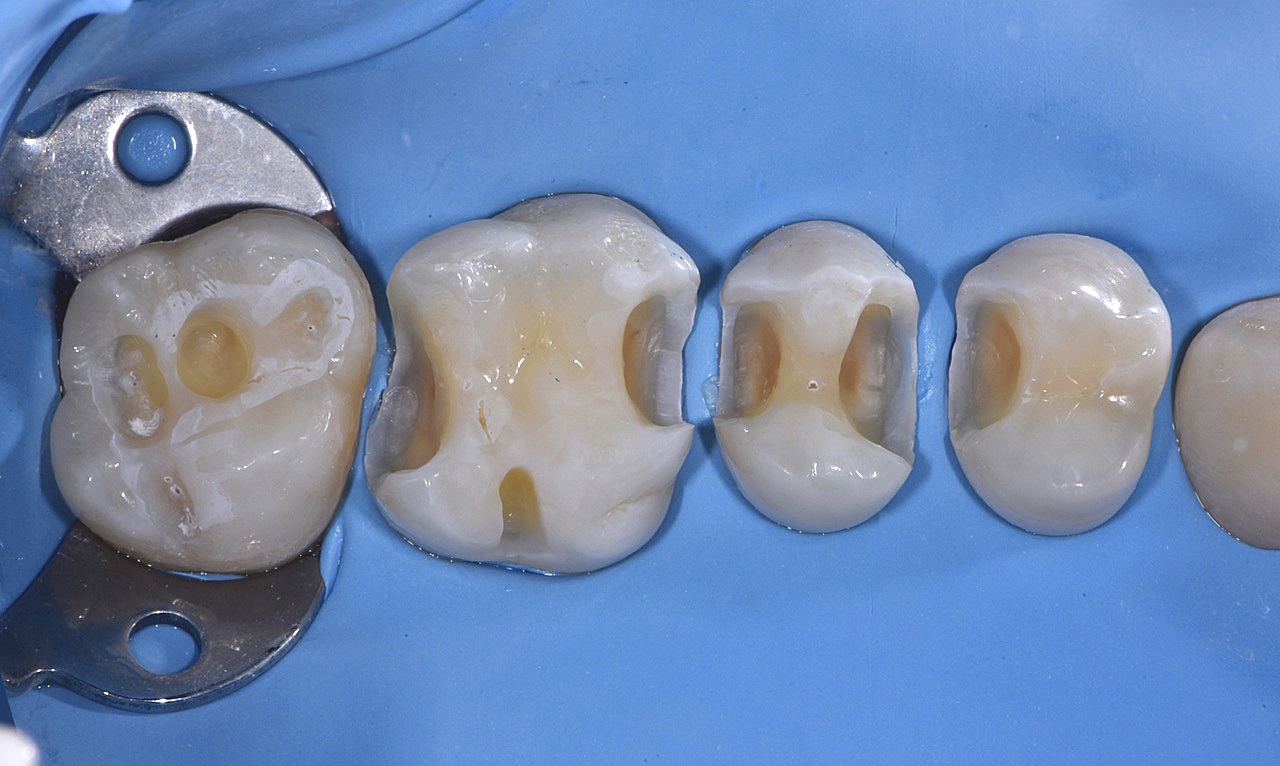

Vengono utilizzati 2 tipi di provvisori: il primo, cementato ai denti vicini, viene utilizzato dal momento dell’estrazione del dente fino ad impianto osteointegrato (circa 6 mesi); il secondo, avvitato direttamente all’impianto, ha una funzione di prova estetica ma soprattutto di guida per la maturazione dei tessuti gengivali peri-implantari portandoli verso la maturazione completa prima di posizionare la corona finale in disilicato di litio.